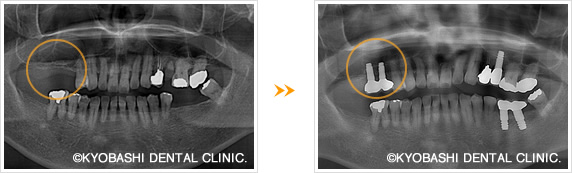

▲当院での下顎前歯のインプラント症例

費用:3本で120万円(税別)

HAインプラントによるソケットリフト(骨造成)の例

ソケットリフト法は、専用の器具を使って上あごの膜(まく)を押し上げて、その部分に人工骨の安全材料を入れて、アゴの骨のの高さを確保する方法です。インプラントを埋入する部分から直接骨を入れて高さをおぎなうので、傷口が小さくて済む利点があります。当院では、患者さんのお体に負担の少ないこのソケットリフト法による骨造成治療で、数多くのインプラントを可能にしております。